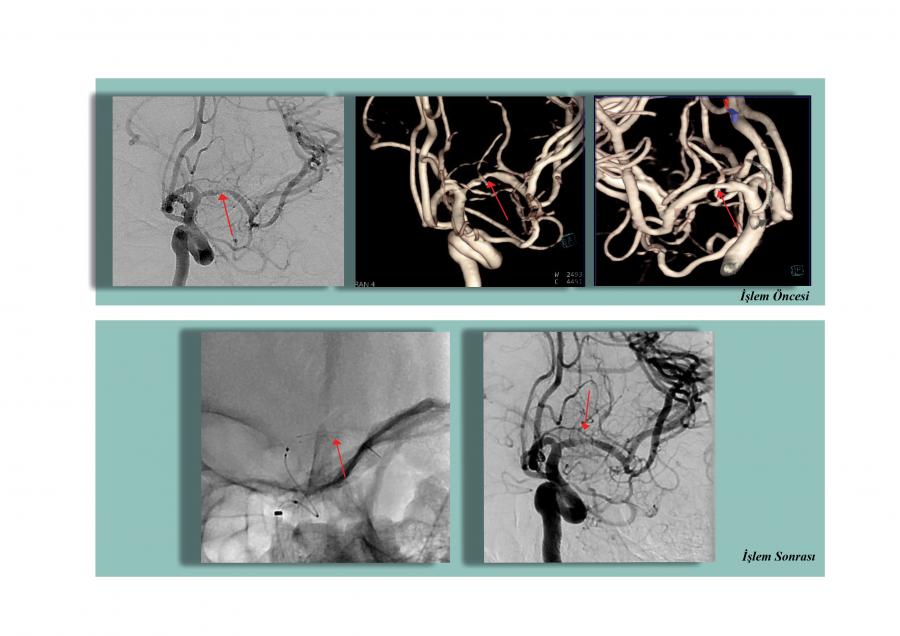

Sağ kolda ve bacakta güç kaybı ve konuşma bozukluğu olan 37 yaşındaki hasta KTÜ Farabi Hastanesi’ne getirildi. Hastamızın yapılan tetkikleri sonucunda inme (felç) geçirdiği anlaşıldı. İnme’nin nedeninin sol beyin damarında yırtılmaya bağlı darlıktan kaynaklandığı anlaşılıp Girişimsel Radyoloji Ünitesi’ne acilen yönlendirildi. Hastamızın beyin damarı, kapalı yöntem ile, kasık damarından girilerek, darlık olan bölümüne stent takıldı. Zorlu geçen girişimsel işlem sonucunda hastamız, büyük ve riskli bir ameliyata gerek kalmadan tüm şikayetleri düzelip, kısa bir sürede şifa ile taburcu edildi.